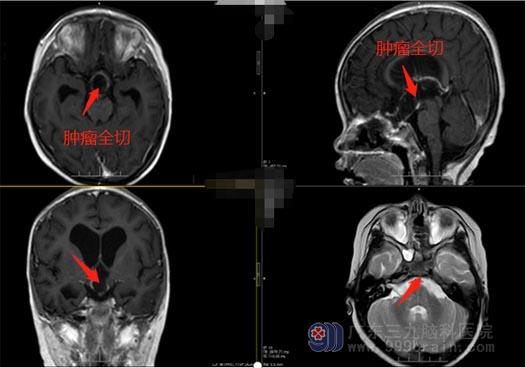

鲁明副院长和神经外五科王国良主任带领治疗团队进行了详细的病例讨论:患儿嗜睡状,哭声间断,呕吐,头颅CT提示鞍内、鞍上、三脑室巨大占位:颅咽管瘤?梗阻性脑积水。患者脑积水严重,家属同意后急诊给予脑室外引流;次日行鞍内、鞍上、三脑室巨大占位切除术,术中见肿瘤起源于垂体柄中央,瘤内减压后沿着肿瘤的包膜切除肿瘤,患者双侧下丘脑被肿瘤侵犯,予肿瘤全切,手术过程顺利。